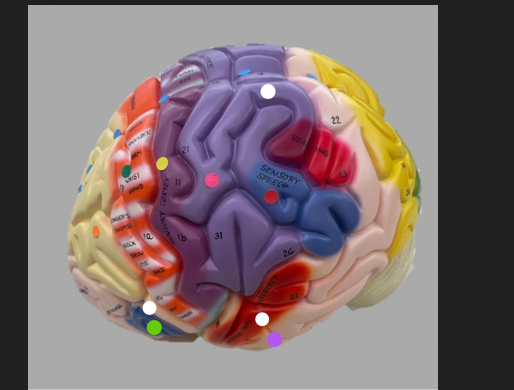

orange dot

frontal lobe

blue dot

longitudinal fissure

dark green dot

precentral gyrus

pink dot

postcentral gyrus

yellow dot

central sulcus

white dot

parietal lobe

light green dot

Broca’s Area

red dot

Wernicke’s Area

orange dot

occipital lobe

blue dot

parieto-occipital sulcus